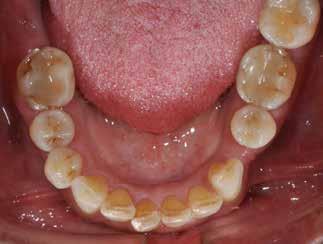

Den kliniske undersøgelse viser ingen symptomer fra muskler eller kæbeled. Ingen ledlyde ved åbne-/lukkebevægelse og ingen udsving ved åbne-/lukkebevægelse. Der er vertikalt overbid (VOB) 3-4 mm, horisontalt overbid (HOB) 1 mm, Angle kl. I med retroklination af såvel over- som underkæbeincisiver

(Fig. 6 A-D). Relativt flad Spee kurve. Ud fra TWES 2.0 graduering har pt. slid af 2. grad i over- og underkæbefront, dog har 1-1 slid af 3. grad. Incisiverne har skarpe incisalkanter med emaljefrakturer og emaljeinfraktioner (Fig. 6 C, D) samt udtalte dentinkonkaviteter incisalt (Fig. 6 E). Posteriort ses slid af 1.-2. grad, og der er mistanke om natlig bruksisme, selvom patienten ikke oplyser dette. Der er såvel attrition som erosion med cuppings på flere molarer samt hævede fyldninger med mindre frakturer (Fig. 6 F, G). Erosiv årsag kan ikke identificeres ud fra kostanamnese. Der ses tydelige slidfacetter i hele tandsættet generelt. Patienten har perfekt mundhygiejne, ingen caries, slimhindeforandringer eller patologiske pocher.

Behandlingsmålet er genopbygning af tænder med tandslid (attrition og erosion). Der ønskes øget facial fylde i både over- og underkæbefront. Bidhævning foretages generelt for at tillade god plasttykkelse på min. 2 mm på alle okkluderende flader og med overdækning af svækkede cuspides med infraktioner posteriort.